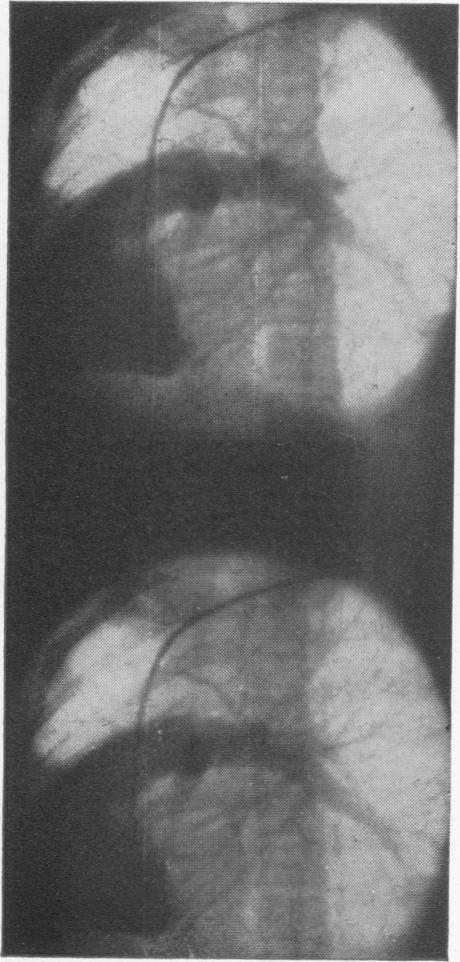

Traumatic rupture of the right main bronchus in an eight-year-old child successfully repaired eight years after injury.

Ann Surg. 1970 Dec;172(6):1039-47. doi: 10.1097/00000658-197012000-00018.